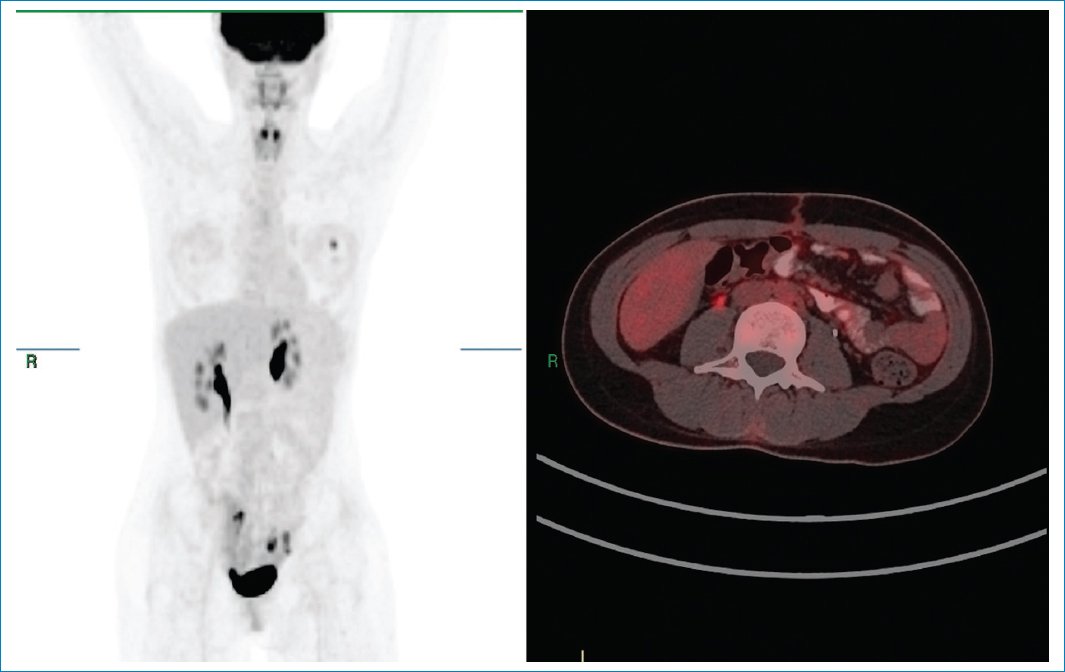

La paciente fue llevada a resección quirúrgica de la masa y se descartó enfermedad multicéntrica por PET-TC con 18F-fluorodesoxiglucosa (18F-FDG) seis meses después del procedimiento quirúrgico (Fig. 3).

Figura 3. PET-TC con 18F-FDG. Desaparece la masa retroperitoneal izquierda por la resección quirúrgica, sin encontrar focos de aumento anormal del metabolismo glucídico. Se descarta enfermedad multicéntrica.